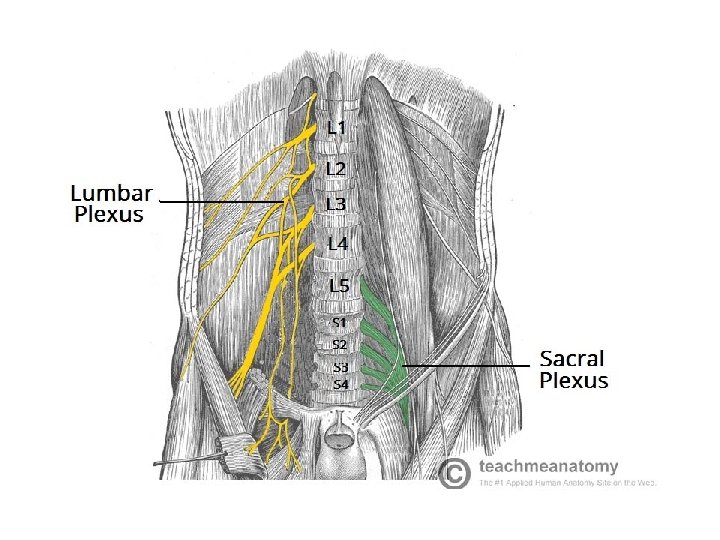

Lumbar plexus • • The lumbar plexus comprises the bundle of nerves which control movement and sensation in the lower extremities. The nerve roots exit the spine at L 1 -5 and S 1 -2. They further branch to form several nerves that descend from the plexus down the thigh and leg into the foot. Only nerves roots and branches, no trunks or cords like the brachial plexus The major branches are the lateral femoral cutaneous, femoral, obturator, and sciatic nerves providing sensation to the medial, lateral and anterior aspects of the thigh.